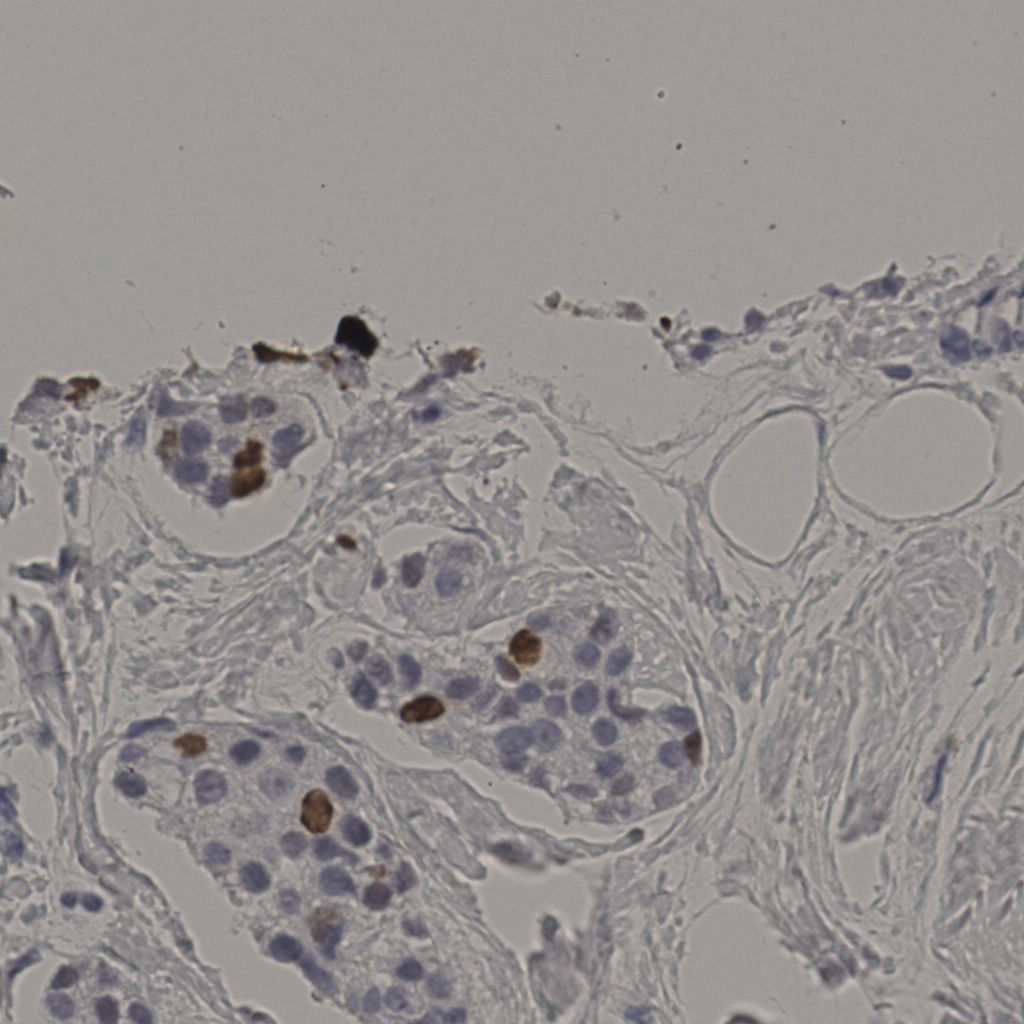

5.31%

Ki67 指数

阴 19502

阳 1093

切片统计

总切片

2970

有效

554

已标记

有效率

19%

标记后

标记前